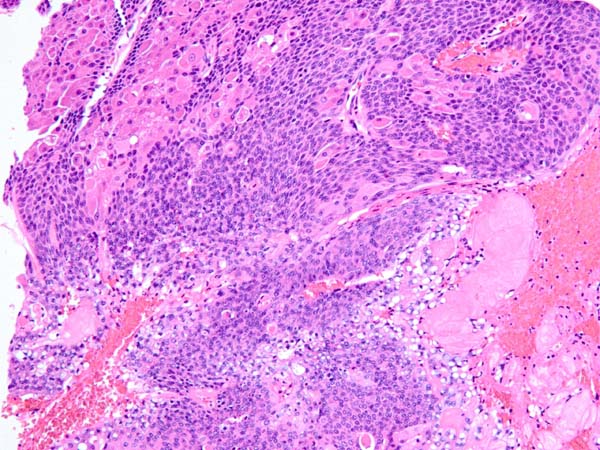

ワンちゃんが乳腺にできた複数のシコリを気にされて来院されました。bilateral mastectomyで対応しました。摘出後の病理組織検査の結果は、「R3-4間腫瘤:乳腺癌(複合型)」でそれ以外は「良性乳腺混合腫瘍」でした。無事元気に退院し、その後再発もなく経過は良好です。よかったね。